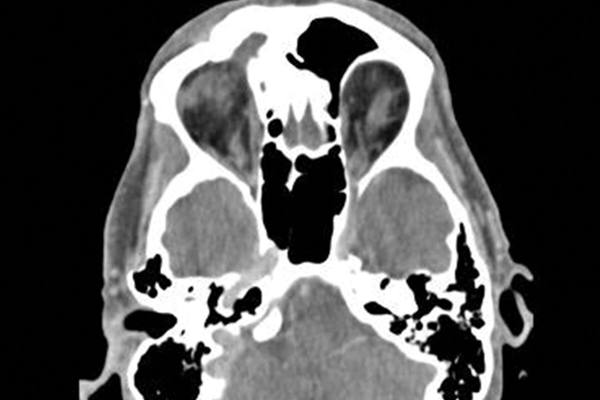

Upper eyelid ulceration as a presenting sign of frontal sinus mucocele